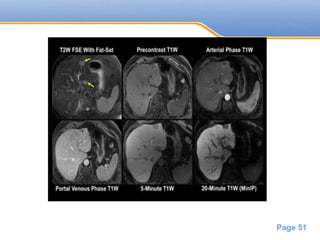

MRI

• Most metastase are hypointense on T1

• Hyperintense on T2

Powerpoint Templates

• #51 Rapid washout is a feature of malignant lesion Most lesion shows less enhancement than surrounding liver

• #52 Two lesions are seen within the lateral segment of the left lobe of the liver (yellow arrows). They appear mildly hyperintense on T2 images and mildly hypointense on precontrast T1 images. On arterial-phase and portal-venous-phase images, the lesions demonstrate rim enhancement; they appear hypointense on 5-minute and 20-minute delayed hepatobiliary-phase imaging. Thin-slab MinIP of the 20-minute delayed images showed no other lesions. This is a straightforward example of the detection and characterization of metastatic disease in the liver. Metastases such as those from colorectal cancer are typically hyperintense on T2 imaging and show rim enhancement on contrast-enhanced T1 imaging. As metastatic lesions contain no functioning hepatocytes, they appear hypointense on delayed hepatobiliary-phase imaging. It is important to review the precontrast T1 images, which often depict these lesions well. Diffusion-weighted imaging showed restricted diffusion within these lesions (not shown).